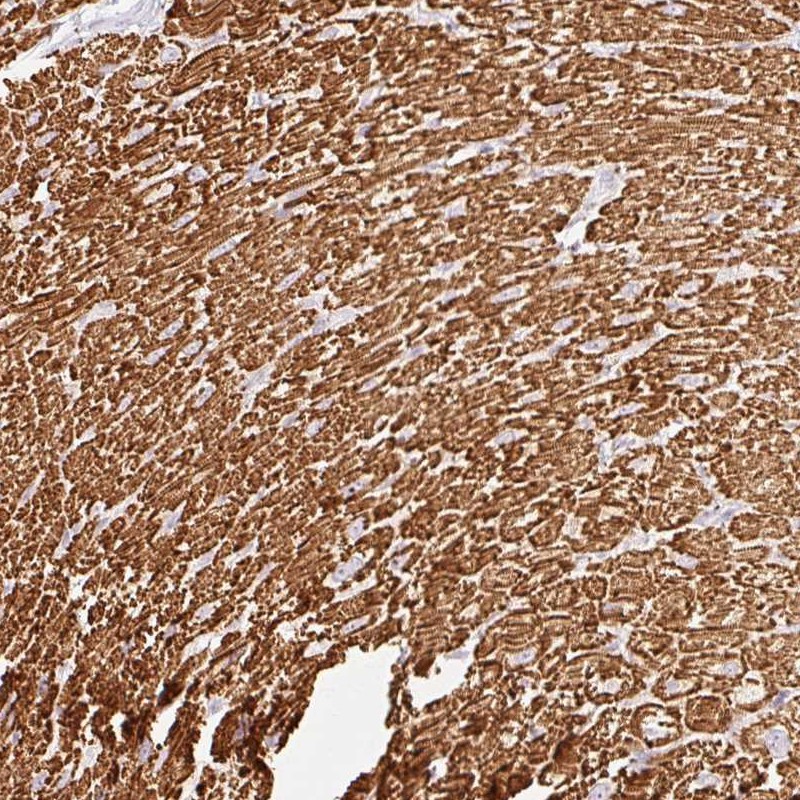

Immunohistochemical staining of human heart muscle shows strong cytoplasmic positivity in myocytes.